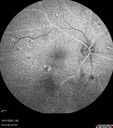

Birdshot Chorioretinitis - Chronic Untreated with Drusen Like Material in Macula92 views72 year old female with vision changes for years just now diagnosed with Birdshot.

Birdshot Chorioretinitis - Chronic Untreated with Drusen Like Material in Macula91 views72 year old female with vision changes for years just now diagnosed with Birdshot.

Birdshot Chorioretinitis - Chronic Untreated with Drusen Like Material in Macula90 views72 year old female with vision changes for years just now diagnosed with Birdshot.